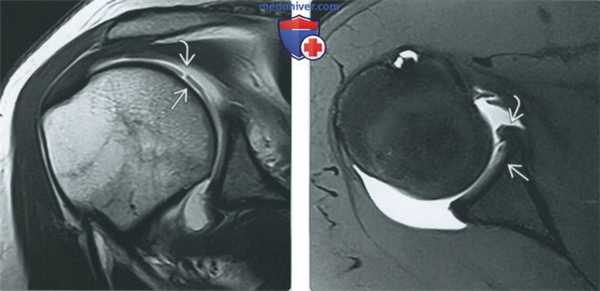

(Слева) МР-артрография в режиме Т1ВИ FS, аксиальный срез: визуализируются последствия неэффективной коррекции дефекта Банкарта. Выявляются небольшая зона утраты костной ткани и распространение контрастного препарата через дефект в восстановленном участке.

(Справа) МР-артрография в режиме PD FS, сагиттальный срез, этот же пациент: отмечается смещение кпереди связочно-хрящевого комплекса. Также выявляются компоненты смещенных шовных фиксаторов. Средняя суставно-плечевая связка не изменена. (Слева) МР-артрография в режиме Т1 ВИ, коронарный срез, этот же пациент: визуализируется смещение восстановленного участка суставной губы. Контрастный препарат распространяется за пределы сустава. Прилежащий отдел суставного хряща почти полностью отслоился. Каналы от шовных фиксаторов выглядят как гипоинтенсив-ныелинии.